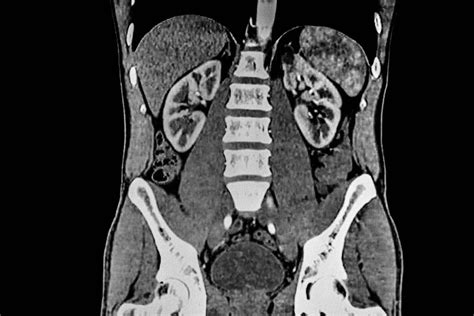

Medical imaging has revolutionized the way clinicians diagnose and treat complex internal conditions, with Computed Tomography Abdomen And Pelvis scans standing at the forefront of modern diagnostic radiology. Often referred to as a CT scan of the lower and middle torso, this imaging modality uses sophisticated X-ray technology coupled with powerful computing to create detailed, cross-sectional images of the organs, blood vessels, and structures within your abdominal and pelvic cavities. Whether you are dealing with unexplained abdominal pain, suspected internal injuries, or monitoring the progress of a known medical condition, understanding what this procedure entails can help alleviate anxiety and prepare you for your diagnostic journey.

A Computed Tomography Abdomen And Pelvis is a non-invasive medical test that helps physicians see inside your body with remarkable clarity. By rotating an X-ray beam around your body, the scanner collects multiple images from different angles, which a computer then reconstructs into comprehensive 3D views. This allows radiologists to identify abnormalities that might be invisible on standard X-rays or even ultrasound scans.